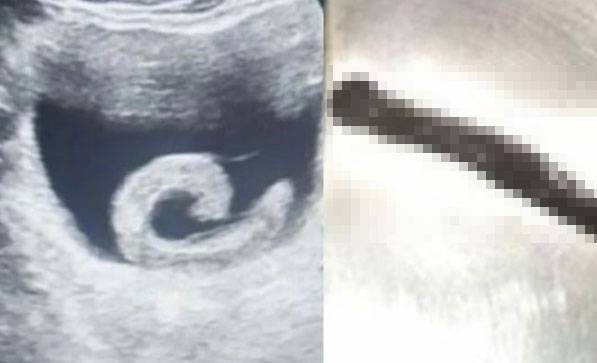

의료진이 초음파와 내시경 검사를 진행한 결과, 남성의 방광 내부에서 길이 5~6cm의 살아있는 거머리 한 마리가 발견됐다. 거머리가 혈액을 흡입하면서 방광 점막은 심하게 충혈되고 부어 있었고, 이로 인해 환자는 극심한 통증과 함께 소변을 볼 수 없었던 것이다.

의료진은 즉시 요도를 통해 내시경 기구를 삽입해 거머리를 제거하는 수술을 진행했다. 시술 이후 남성은 정상적으로 소변을 볼 수 있게 됐으며, 현재 추가 합병증 없이 회복 중인 것으로 알려졌다.